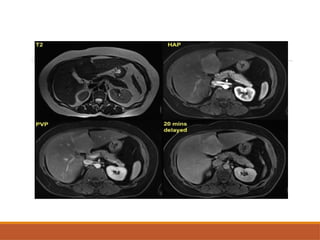

MRI

T1WI: Iso-intense to normal liver parenchyma.

T2WI: Iso to slightly hyper-intense.

Central scar is hypointense inT1WI & hyperintense

in T2WI

T1WI : variable (fatty change, internal

fibrosis,hge)

T2WI : hyperintense

Capsule : hypo in T1 &T2WI

CEMR : similar to CECT

MRI T1WI: Hypo-intense relativeto liver parenchyma. T2WI: Significantly hyperintense –producing light bulb appearance. T1C+(GD):Nodular enhancement

MRI T1WI : variable(fatty change, internal fibrosis,hge) T2WI : hyperintense Capsule : hypo in T1 &T2WI CEMR : similar to CECT

• #13 Axail T1 and T2 weighted images showing T1 hypointense and T2 hyperintense tumour in segment 6 of right lobe suggestive of giant hemangioma

• #20 There is a T1 and T2 isointense lesion in segment 4 a The lesion is uniformly avid enhancing in arterial phase and iso/slight hyperintensity during the portal venous phase. The 20 minutes delayed image demonstrate persistent intralesional hyperintensity and this confirms the diagnosis of FNH.

• #33 Axial t2 weighted image showing hetrogebous intensity lesion in right lobe of liber with heterogenous enhancenment in arterial phase nafd washout of contrast in portal venous phase